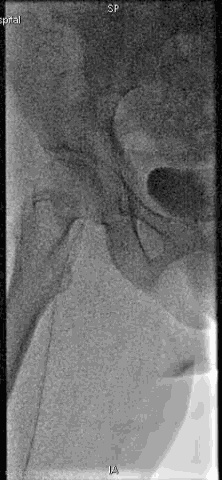

手术过程

抽吸结果

病例小结